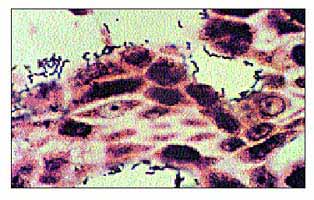

Биоптат слизистой оболочки антрального отдела желудка 43-летнего Б.Маршалла.

10-й день эксперимента по самозаражению.

Серебрение по Вартину-Стэрри. Увел. 640.

Отчетливо видны изогнутые бактериальные клетки на поверхности клеток эпителия желудка.